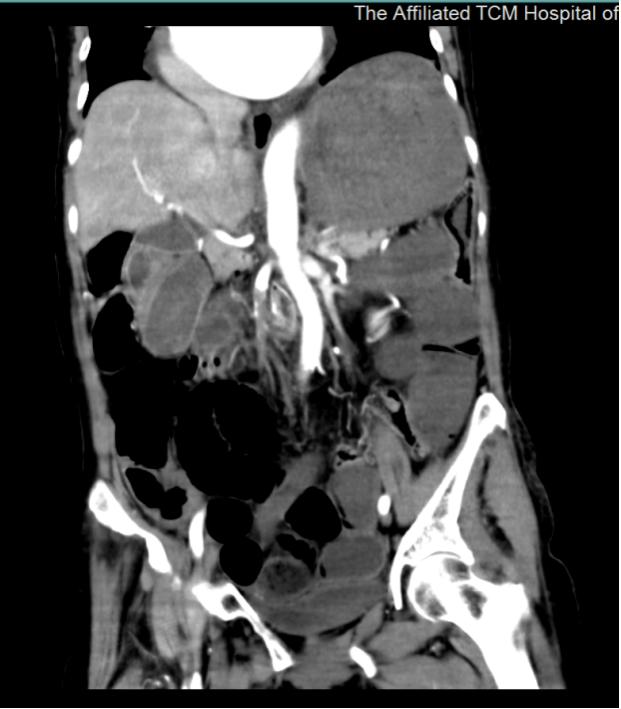

全腹CT结果:1.考虑肠梗阻,回肠远段(近回盲部处)肠管壁处透亮气体影,肠管内气体?不除外肠壁坏死积气可能,请结合临床。乙状结肠术后改变。2.肠系膜上动脉血栓形成;门静脉及肠系膜上静脉管腔内有脂肪密度影,请结合临床考虑。3.肝内多发小囊肿;肝左叶部分胆管积气。4.胆囊多发结石。左肾囊肿。5.子宫内金属密影,考虑节育器。6.所及心脏增大。

患者既往有心脏不适,未至医院检查,结合目前影像学检查,考虑是房颤导致血栓脱落,血栓堵塞肠系膜上动脉引起肠坏死可能。急诊外科医生迅速向上级医师汇报情况,外一科吴江平主任及杨振淮副主任指示,肠系膜上动脉血栓形成是外科急危重症,尽早行剖腹探查,全力抢救病人!

送入手术室时,患者出现了血压下降,心监提示心率增快,房颤率。李关宁副主任医师主持抢救,考虑肠系膜上动脉血栓形成是外科急危重症,房颤引起血栓并不是短时间形成,CT提示肠坏死可能,需要尽快剖腹解除感染!分秒必争,麻醉师及外科医师顶住压力,在抗休克同时进行手术。

打开腹腔瞬间,一股腐臭味扑面而来,在场的人惊呆了。患者全程小肠及升结肠瘀黑肠管扩张坏死,横结肠中段及远端结肠无明显坏死,胃储留扩张、十二指肠明显扩张。李关宁副主任医师及耿燚副主任医师判断,此时对肠系膜上动脉进行切开取栓已经无意义, 切除坏死肠管才可以挽救患者生命。随即两人熟练为患者切除坏死全小肠及右半结肠,行十二指肠及结肠吻合。术后患者转ICU进一步复苏。